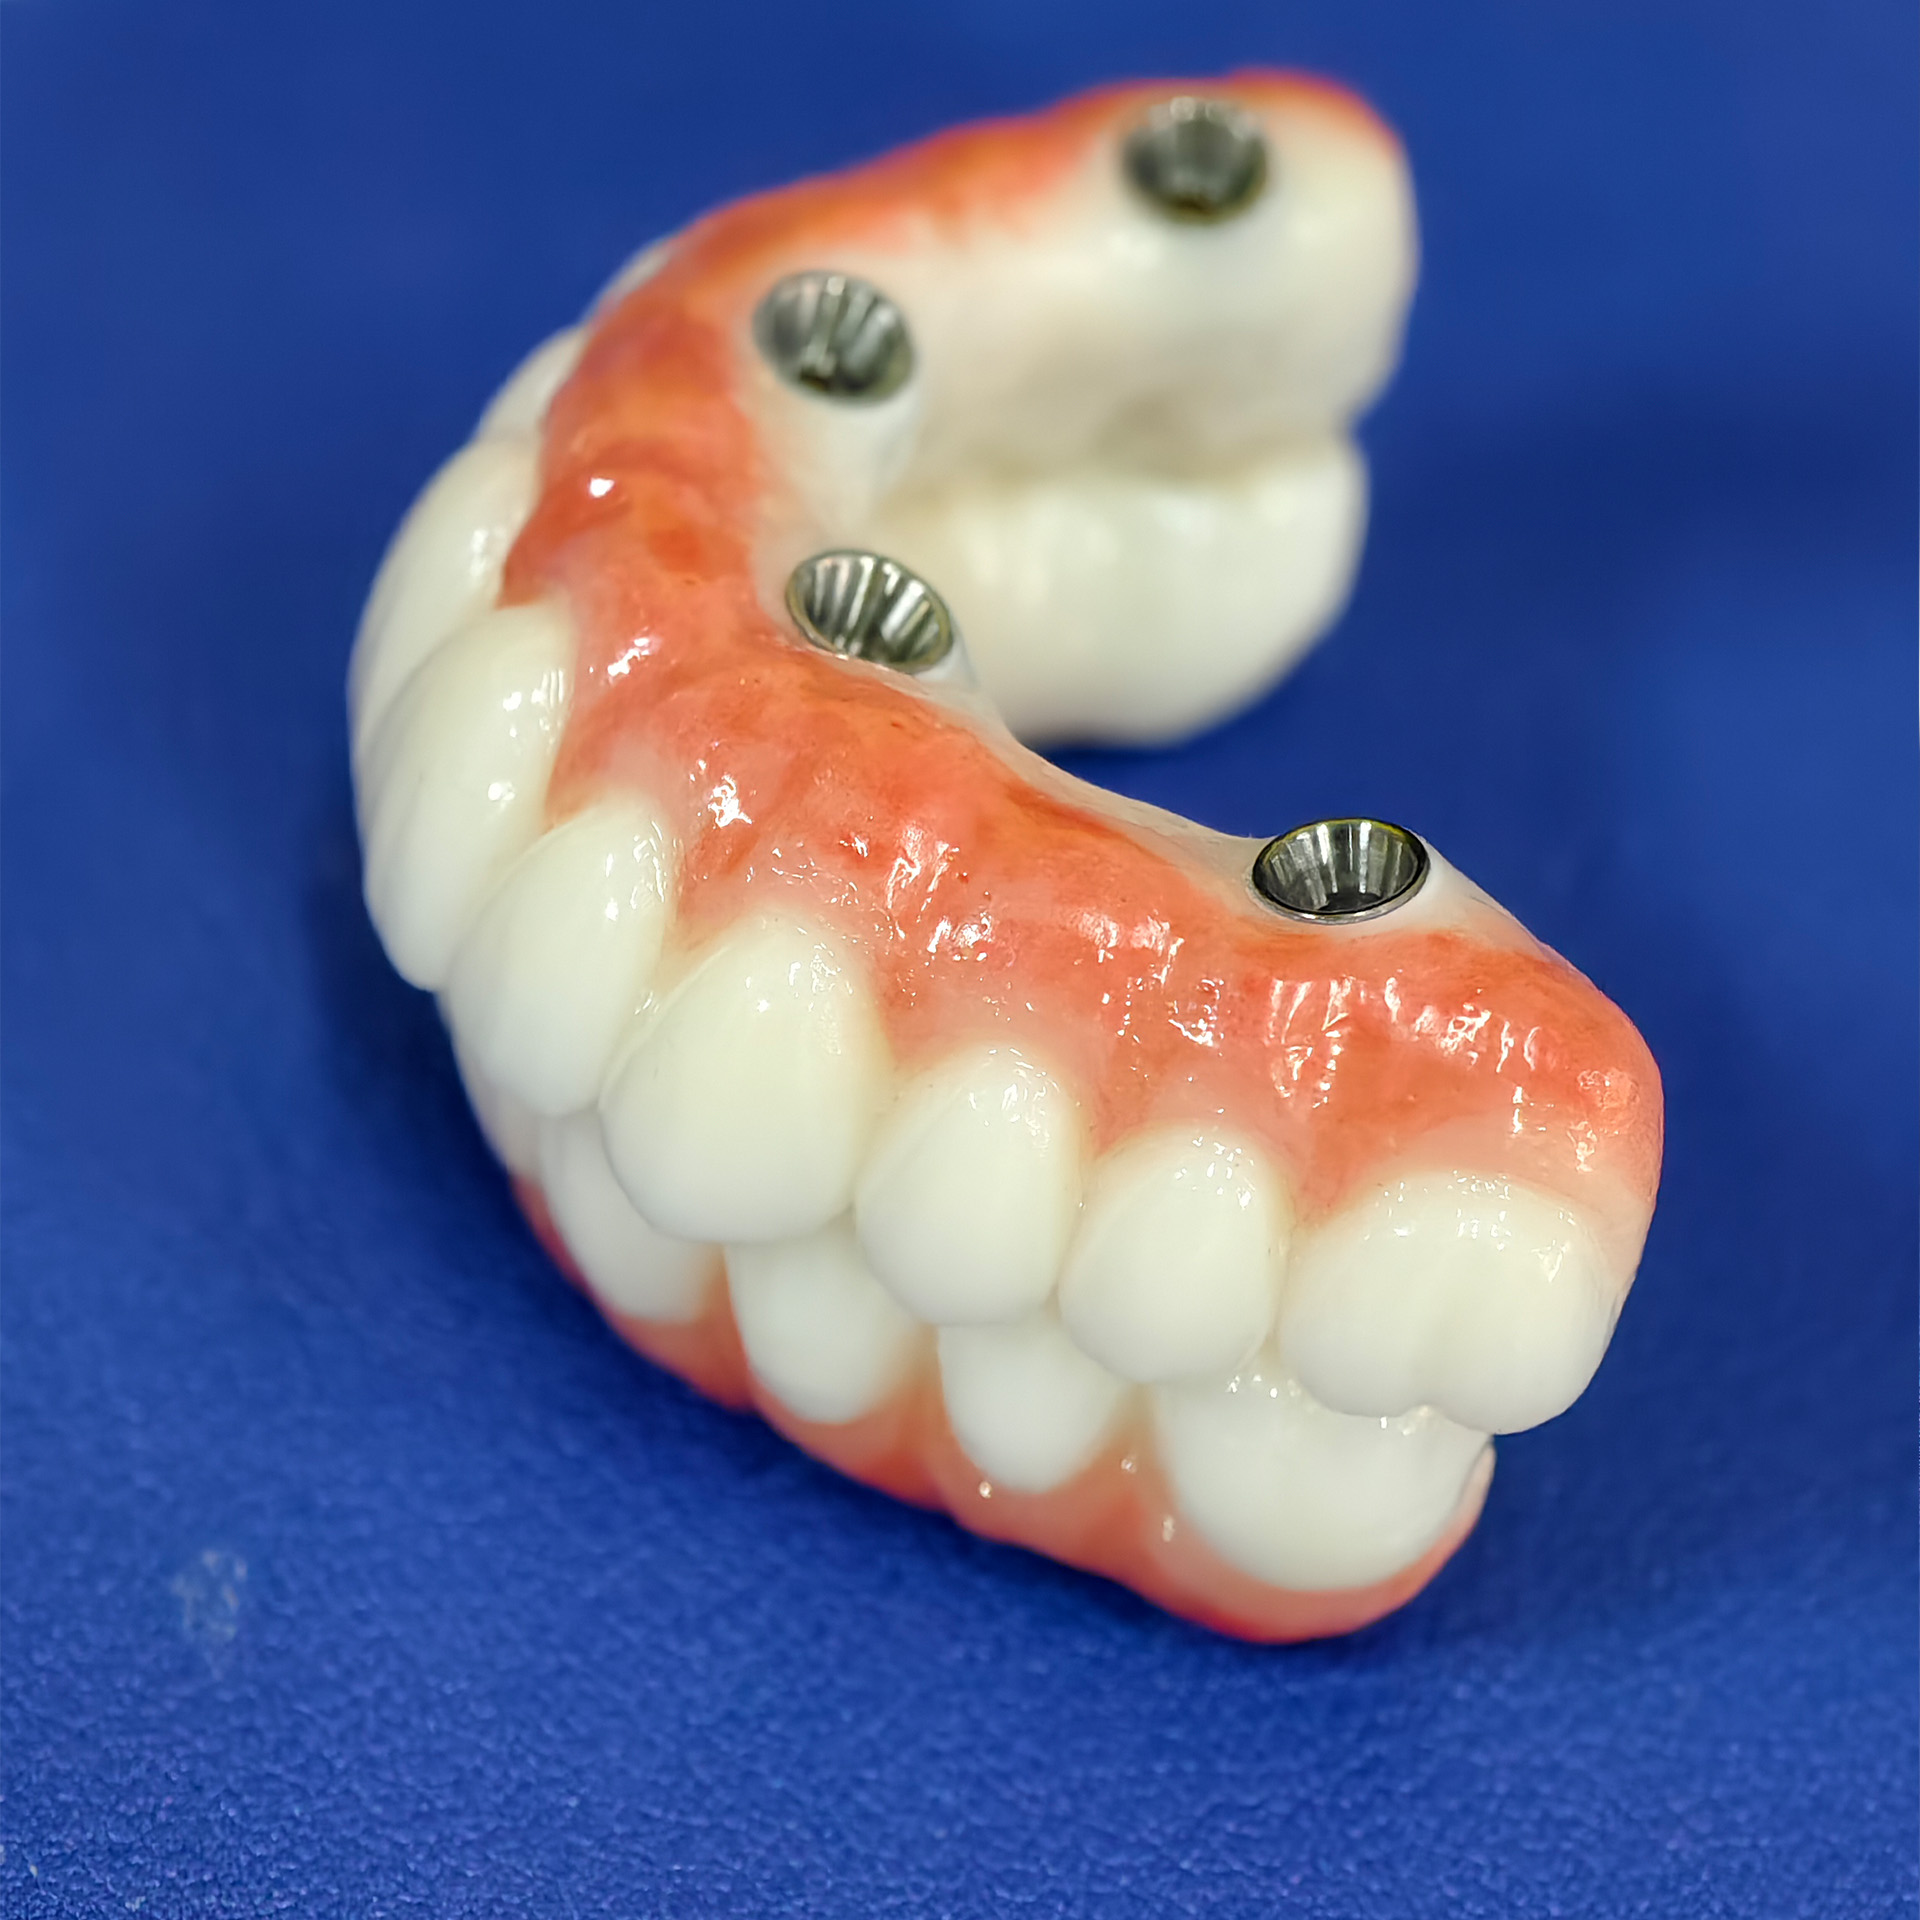

All-on-4 is a dental implant

All-on-4 is a dental implant technique that uses four strategically placed implants to support a Full arch of teeth, typically for patients who have lost all or most of their teeth. This approach offers a cost-effective and efficient solution compared to traditional dental implants, often eliminating the need for bone grafting.

All-on-4 involves placing four dental implants in the jawbone (either upper or lower) to support a fixed denture or bridge.

The implants act as artificial tooth roots, providing a stable foundation for the replacement teeth.

The back implants are often angled to maximize bone contact and avoid the need for bone grafts in some cases.